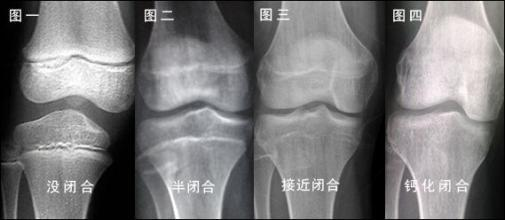

身高增长依赖长骨两端骨骺软骨细胞的分裂骨化,骨骺线闭合则生长停止

核心标准:骨龄检测,拍左手腕骨X光片查看骨骺状态